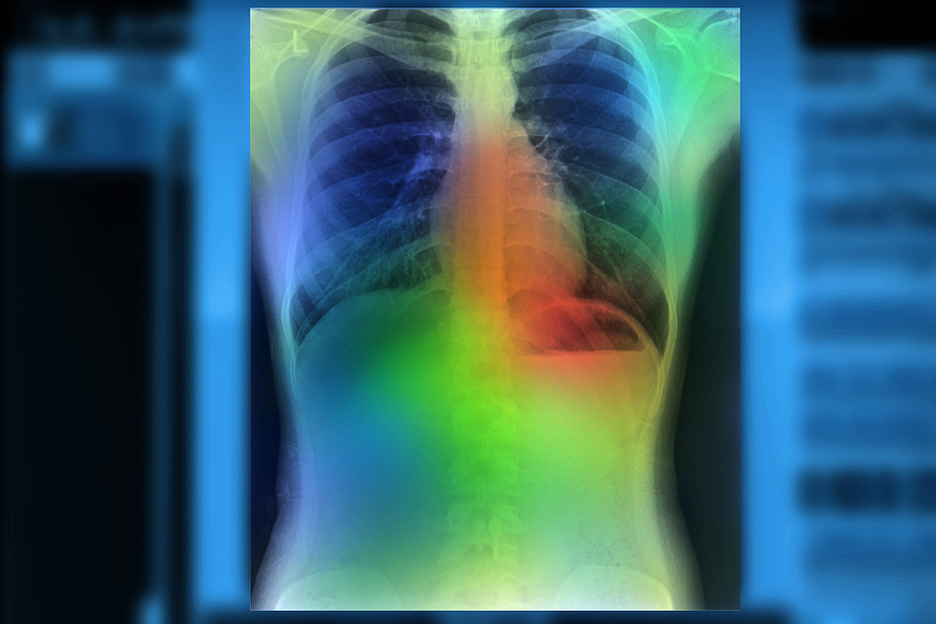

Основной функцией системы диагностики «Сайберия» является распознавание патологических изменений на медицинских изображениях. Это происходит с помощью технологий ИИ.

Эффективность работы системы обеспечивается методом анализа медизображений КТ, основанного на технологии компьютерного зрения и машинного обучения. Именно этот метод выбрал разработчик для своего проекта.

С помощью инновационного способа происходит автоматическое распознавание различных патологических процессов на медицинских изображениях. Оперативная и точная подсказка нейросети позволяет врачу быстро и точно поставить диагноз пациента. Авторы разработки добились высокой точности работы машины — она в 95% случаев ставит верные предварительные диагнозы. Причем весь процесс занимает всего 45 секунд. К сегодняшнему дню в системе было обработано уже более 10 тыс. КТ-исследований.

Во время пандемии коронавируса, в 2020 году, система была успешно использована для прикладных задач для выявления признаков вирусной пневмонии коронавируса и узелковых образований в легких.

Алгоритмы, разработанные командой Сайберия с применением ИИ, позволили автоматизировать диагностический процесс и анализировать данные КТ с высокой точностью. Программное обеспечение автоматизирует процесс принятия решений на основе изображений КТ, и  дает рекомендации врачам обратить внимание на тех, кто из пациентов скорее всего болен коронавирусной пневмонией, а кто страдает от других форм воспаления легких.

Точность нейросетевой модели составляет 95% вероятности того, что болеющий короновирусной инфекцией будет правильно идентифицирован среди других случаев пневмонии.

Чувствительность — 87% — это вероятность того, что случай с COVID-19 будет правильно идентифицирован как случай с  SARS-CoV-2.

Специфичность — 97% — это вероятность того, что не ковидный пациент будет правильно продиагностирован, как не болеющий коронавирусом.

Согласно рекомендациям экспертов Московской службы здравоохранения и ВОЗ, в настоящее время для первичной диагностики коронавирусной пневмонии используется компьютерная томография. Основным симптомом этого заболевания является поражение легких в виде интерстициальной пневмонии. Поскольку интерстициальную пневмонию трудно диагностировать даже опытным радиологам, программное обеспечение помогает в раннем выявлении этого заболевания, которое может протекать бессимптомно. При заболевании этим новым видом пневмонии, самым опасным осложнением становится острый респираторный дистресс-синдром. Для эффективного лечения вирусная пневмония должна быть выявлена на ранней стадии.